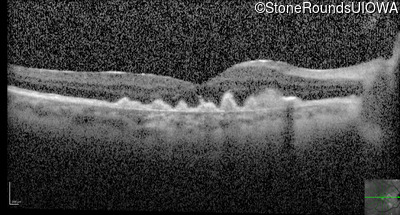

Visit at age: 60 years (Visit 2)

Optical Coherence Tomography - Right - 20/100

Exemplar / OCT Stack

OCT Stack